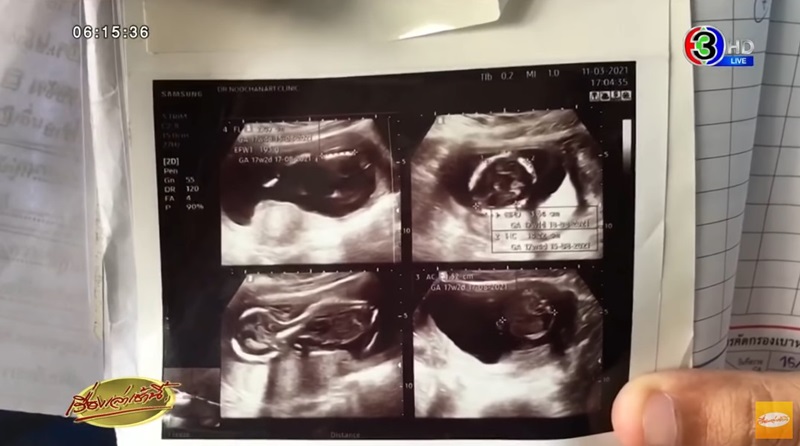

แต่หลังจากเวลาผ่านไป หน้าท้องกลับไม่มีอาการยุบหรือลดลงเหมือนคนปกติ และรู้สึกเหมือนมีอะไรดิ้นในท้อง เธอคิดว่าอาจมีอาการแทรกซ้อนบางอย่าง จึงไปหาหมอที่คลินิก จนกระทั่งพบว่าในท้องยังมีเด็กอยู่ จึงตกใจและอึ้งกับเหตุการณ์ที่เกิดขึ้นเป็นอย่างมาก

วันที่ 16 มีนาคม 2564 เรื่องเล่าเช้านี้ รายงานว่า น.ส.ศิริวรรณ อายุ 19 ปี เข้าร้องเรียนผู้สื่อข่าวกรณีช่วงเดือนธันวาคม 2563 เธอตั้งครรภ์ได้ 2 เดือน จากนั้นมีอาการตกเลือดจึงเดินทางไปพบแพทย์ที่โรงพยาบาลรัฐแห่งหนึ่งในพื้นที่ อ.ศรีราชา จ.ชลบุรี โดยแพทย์วินิจฉัยว่าเกิดจากครรภ์เป็นพิษ อาจมีอาการแทรกซ้อนอันตราย จึงเห็นสมควรให้ทำแท้งหรือยุติการตั้งครรภ์ จึงได้มีการขูดมดลูกและกลับบ้านมาพักฟื้น